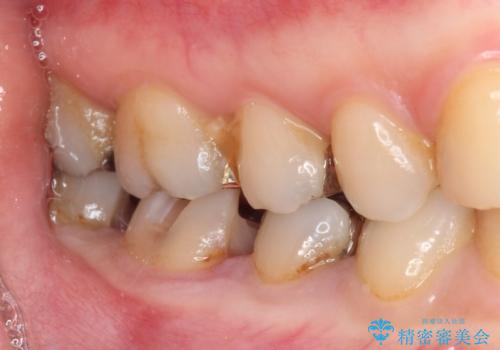

下の奥歯の虫歯をゴールドインレーで治療

- 奥歯の虫歯を心配して来院した患者様です。

レントゲン写真から、以前治療した詰め物の下に虫歯があることがわかりました。

精度が高く、虫歯の再発リスクの低いゴールドインレーで治療を行うこととしました。